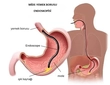

Ciğerde yara veya karaciğer yarası, genellikle karaciğerin iltihaplanması, hasar görmesi veya enfeksiyon sonucunda meydana gelen bir durumdur. Karaciğer, vücudun en büyük iç organlarından biri olup, birçok önemli işlevi vardır. Bu makalede, ciğerde yara belirtileri, nedenleri, tanı yöntemleri ve tedavi seçenekleri ele alınacaktır. Ciğerde Yara Nedenleri Ciğerde yara oluşumuna neden olabilecek birçok faktör bulunmaktadır. Bunlar arasında:

Bu nedenlerin her biri, karaciğerin yapısında ve işlevselliğinde değişikliklere yol açarak yara oluşumunu tetikleyebilir. Ciğerde Yara Belirtileri Ciğerde yara belirtileri, genellikle hastalığın evresine ve ciddiyetine bağlı olarak değişir. Aşağıdaki semptomlar, karaciğer yarası olan bireylerde sıkça gözlemlenebilir:

Bu yöntemler, karaciğerdeki hasarın boyutunu ve nedenini belirlemeye yardımcı olur. Tedavi Seçenekleri Ciğerde yara tedavisi, yaranın nedenine ve ciddiyetine bağlı olarak değişiklik göstermektedir. Genel tedavi seçenekleri şunlardır:

Tedavi süreci, doktor tarafından belirlenen bir plan çerçevesinde ilerlemeli ve hastanın durumuna göre düzenlenmelidir. Sonuç Ciğerde yara, ciddi sağlık sorunlarına yol açabilen bir durumdur. Belirtilerin farkında olmak ve zamanında tıbbi yardım almak, karaciğer sağlığını korumak için önemlidir. Hastalar, sağlıklı yaşam tarzı seçimleri yaparak ve düzenli kontrollerle karaciğerlerini koruyabilirler. Ekstra Bilgiler Karaciğer sağlığını korumanın yolları arasında: